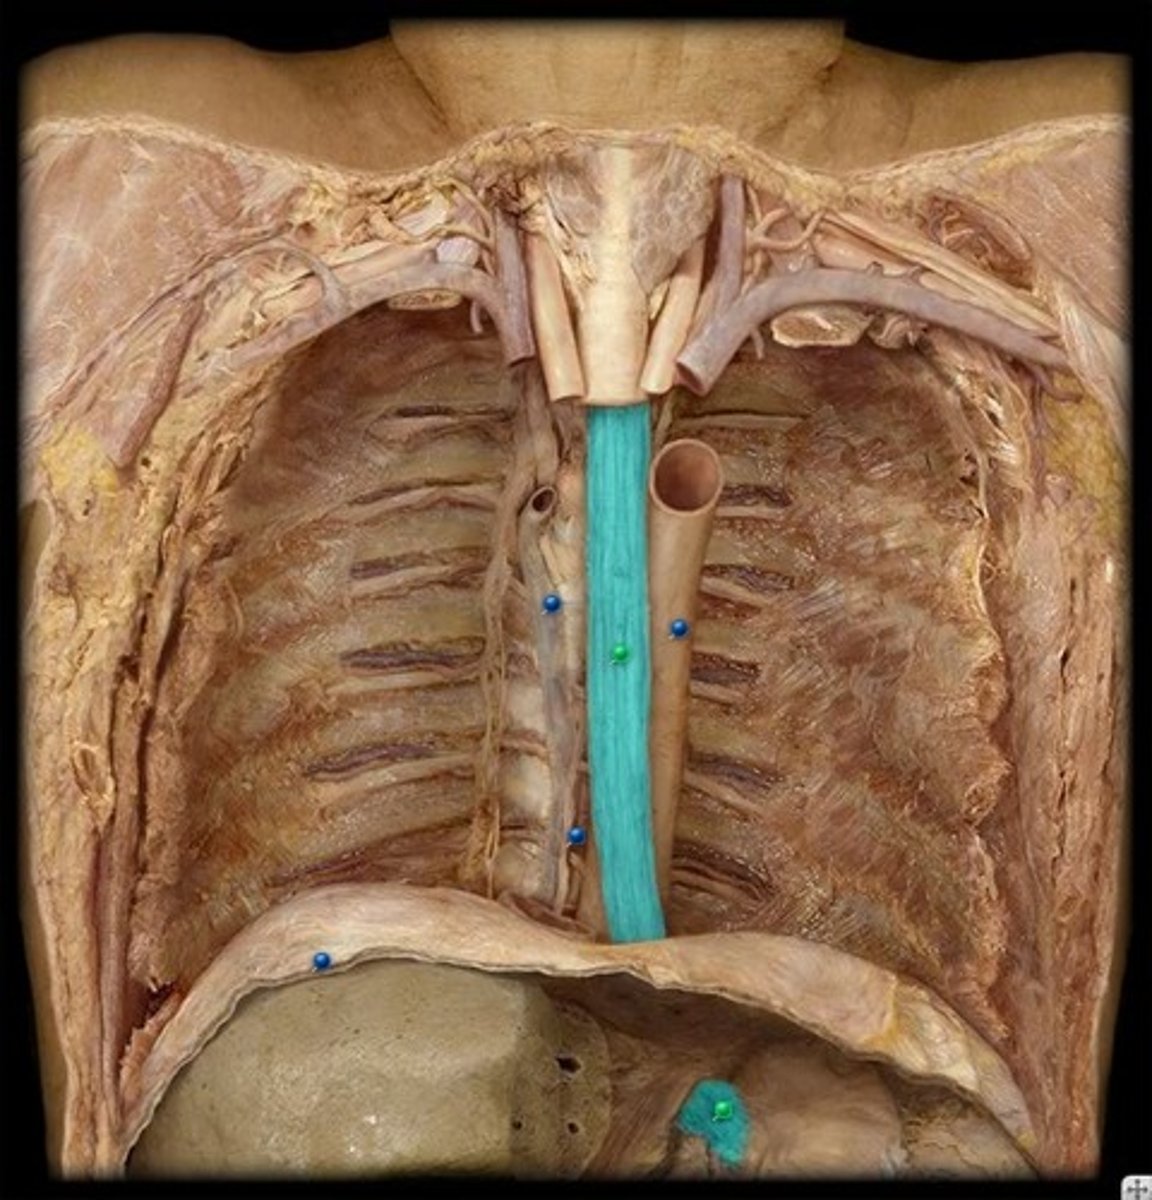

vagal trunks (left and right)

esophagus

azygos vein

descending aorta

thoracic duct

posterior intercostal arteries and veins

intercostal nerves

sympathetic trunk and chain ganglia